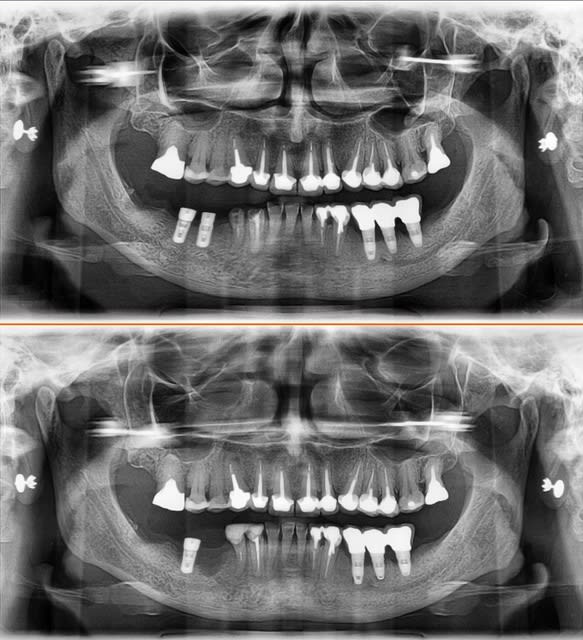

Patiente 57 ans, non fumeuse, un peu bruxo

les implants secteur 3 ont été posé il y a 4 ans, perte osseuse la première année, puis stable depuis...

je pose deux implants à droite... la patiente reviens avec l'implant manquant sur la radio dans la main ... :( :( :(

1 mois entre les deux pano

Diagnostic, os très dense, beaucoup de mal au forage.

Je pense que j'ai échauffé la corticale et entraîné une lyse rapide...

A gauche je sais pas quels sont les implants ... mais il y a eu une perte rapide aprés la pose, et c'est stable depuis 2009...

a droite je pose du Biocom MIS

C'est la première fois que ça m'arrive sur environ 300 implants... et on peut pas dire que ce soit un cas limite...